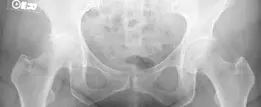

3. التقييم الإشعاعي والتصوير (صور 3.14، 3.15، و 3.16):

التصوير بالأشعة السينية هو الأداة الرئيسية لتأكيد تشخيص التهاب المفاصل وتقييم شدته.

صورة 3.14:

صورة بالأشعة السينية الأمامية الخلفية (AP) قبل الجراحة تُظهر التهابًا شديدًا في مفصل الورك الأيمن مع فقدان كبير لمساحة المفصل، وتكون نتوءات عظمية، وتصلب العظم تحت الغضروف.

صورة 3.15:

صورة بالأشعة السينية الجانبية قبل الجراحة تُظهر نفس التغيرات المذكورة أعلاه، مؤكدة شدة التهاب المفصل.

صورة 3.16:

صورة بالأشعة السينية الأمامية الخلفية قبل الجراحة مع قالب تخطيطي. يوضح التخطيط المسبق لجذع الفخذ ذي الإزاحة القياسية بقطر 15 ملم وكأس حقي بقطر 52 ملم. كما لوحظ وجود تباين في طول الساق بمقدار 4.7 ملم.